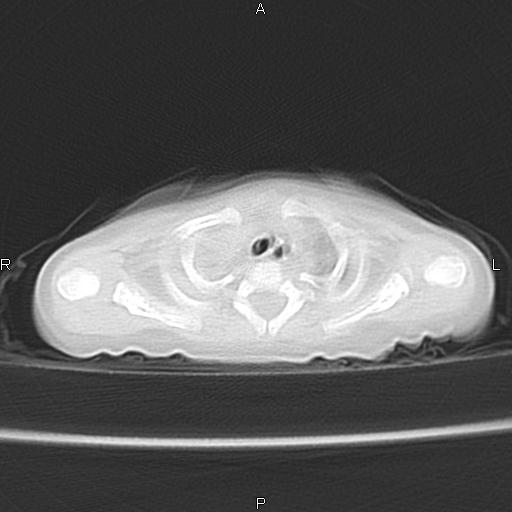

以下是引用aa13877358820在2010-7-26 12:35:00的发言:[br]男性,三个月,卧位胸片,咳嗽、气促、发热14天,两肺闻及细小水泡音。[br]